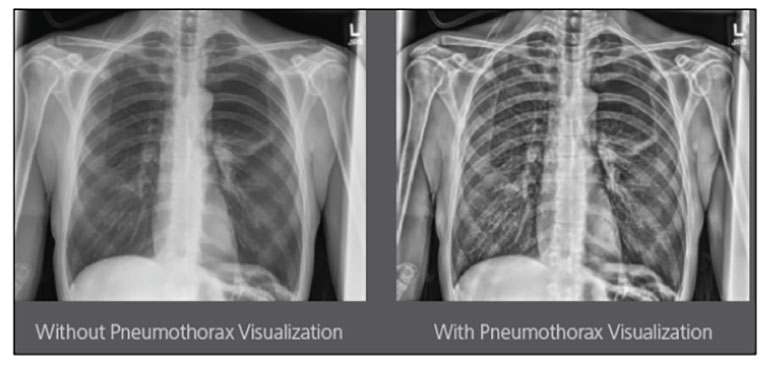

Carestream Introduces New Software Update to Boost Diagnostic Accuracy

Carestream today announced the latest update to its Image Suite V4 Software, MR 11: a series of enhancements to help improve customer confidence and increase diagnostic accuracy [...]